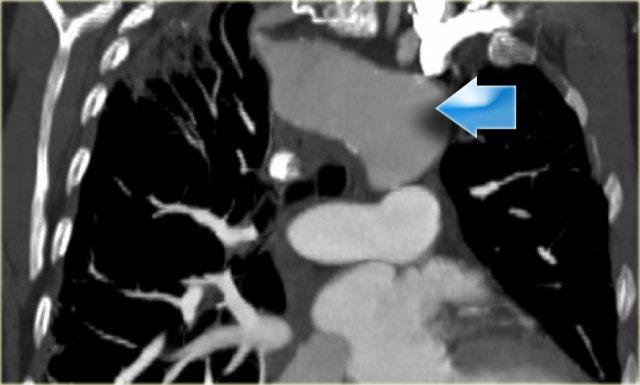

On the left a 78 year old woman with dysphagia.

There is consolidation in the right upper lobe, maybe due to aspiration.

There is a dilated vessel that compresses the esophagus and it originates from the left-sided aorta, i.e. an aberrant right subclavian artery.

On the left the same patient with dilated aberrant right subclavian artery.

Coronal reconstruction.